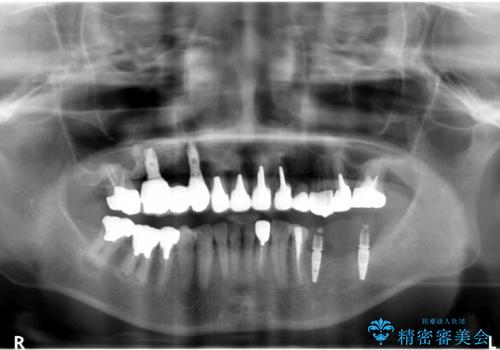

全顎的 虫歯治療 インプラント補綴

今後延々と治療を繰り返さないために、全ての銀歯を外し虫歯を丁寧に取り切り、根管治療を行い、残せない歯は抜去を行った上でインプラント治療を行っていくことで全体的な治療を計画していくこととなりました。

工程数が多かったため治療期間はかかりましたが、しっかりと安定した噛み合わせ、審美的な口腔内環境を達成することができ大変満足していただくことができました。